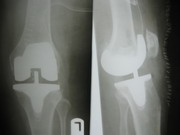

Knee Joint Replacement